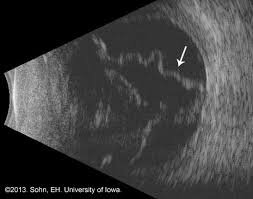

“الٹراساؤنڈ کی مدد سے جب معائنہ کرتے ہیں تو اکھڑا ہوا پردہ کیسے نظر آتا ہے وہ نیچے کی تصویر میں دکھایا گیا ہے”